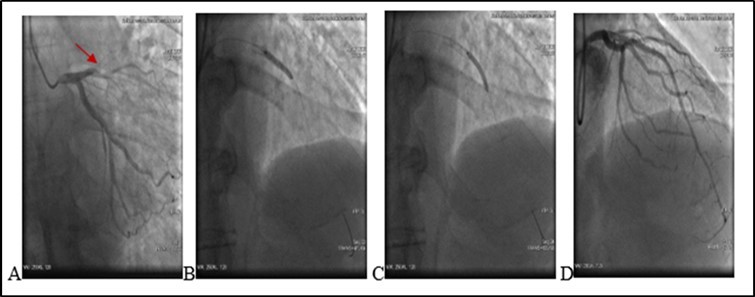

On ECG : HR 78 . Sinus rythm. ST segment elevation I, aVL, V1- V5 (2mm at the J-point). Q wave in V2-V4 leads. T/A 180/70 mm Hg. Patient refused missing of presribed medications. Due to severe chest pain, ECG data and haemodynamic instability an urgent PCI was performed. It revealed a stent thrombosis in LAD - early stent thombosis (1). Circumflex Coronary artery (CX) and Right Coronary artery (RCA)- without significant changes (see Figure 2).

Figure 2.(20.06.2020) .A. Occluded stent due to early thrombosis (red arrow). B.C Balloon angioplasty and stenting. D. Final result.

After administration of a 180 mg loading dose of ticagrelor and an intravenous bolus of 10.000 units heparin, left main coronary artery was cannulated with a 6F EXB4 guiding catheter and a 0.014’’ floppy guide wire was advanced in LAD. Coronary artery recanalisation performed successfully. After baloon angioplasty with 3.0X12 mm baloon-catheter, in proximal and medial segments intraluminal filling defect was observed – reduced contrast dencity and heziness and two BMS were overlaped - 3.5X24 mm and 3.0X24 mm respectively. Postdilation was performed at the end of the procedure.TIMI score was 3. Procedure performed without any techincal complication during coronary intervention. Patient was stable and he was transferred to the Intensive Care Unit.